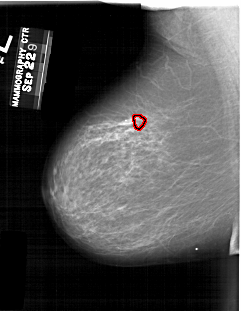

FILE: A_1260_1.LEFT_MLO.OVERLAY

TOTAL_ABNORMALITIES 1

ABNORMALITY 1

LESION_TYPE MASS SHAPE ARCHITECTURAL_DISTORTION MARGINS ILL_DEFINED

ASSESSMENT 4

SUBTLETY 2

PATHOLOGY MALIGNANT

TOTAL_OUTLINES 1

BOUNDARY